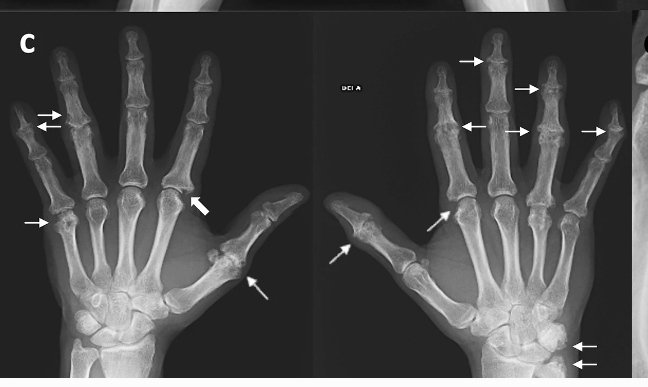

πŸ‘‰c.Polyarticular and asymmetrical PsA on hands with interphalangeal joints involved showing

πŸ‘‰articular space narrowing and erosions (thin arrows),

πŸ‘‰one of them is a Ξ© shaped erosion (thick arrow)